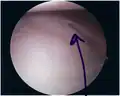

Bankart lesion seen at arthroscopy